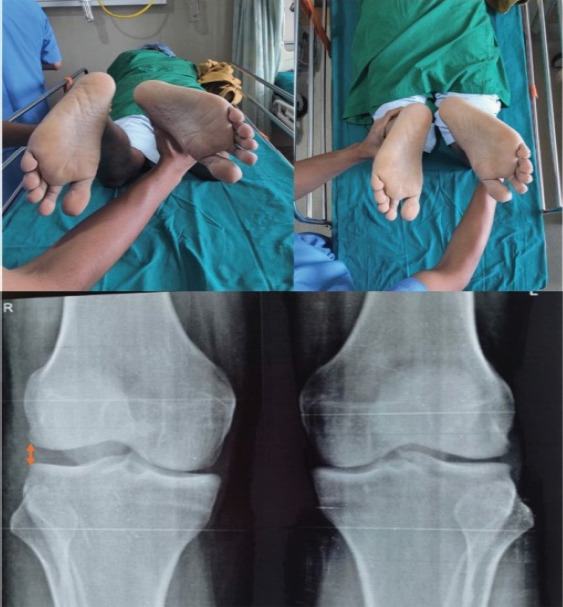

后外侧角(PLC)损伤通常与交叉韧带撕裂有关。历史上被称为膝盖的“阴暗面”,进步极大地提高了我们对PLC的理解,今天提供了各种管理选择。病例报告:我们提出的情况下,44岁的男性合并PLC和后十字韧带(PCL) 2级损伤。患者采用开放解剖arciero技术与胫骨前肌同种异体移植物进行孤立PLC重建。在随后的随访中,患者表现出良好的膝关节功能结果,无不稳定,易于进行常规活动,包括低至中等要求的体育活动。结论:PLC和PCL合并损伤的有效管理需要早期识别PLC损伤和具体病例的管理方法,考虑患者的病情、外科医生的专业知识和移植物的可用性等因素。同种异体移植物是自体移植物重建PLC的可行选择,与后者相比具有几个优点。

Case report: We present the case of a 44-year-old male with a combined PLC and posterior cruciate ligament (PCL) Grade 2 injury. He was managed with an isolated PLC reconstruction using an open anatomical Arciero-based technique with a tibialis anterior allograft. At subsequent follow-ups, the patient was shown to have excellent knee functional outcomes, no instability, and ease of performing regular activities, including low to moderate-demand sporting activities.